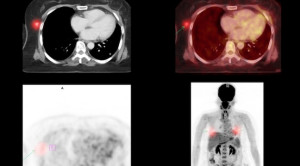

Pemeriksaan kedokteran nuklir bermanfaat untuk mendeteksi proses infeksi atau inflamasi di tahap awal/dini, sehingga dapat berperan dalam diagnosis penyakit tuberkulosis. Seperti diketahui,...(Baca Selengkapnya)